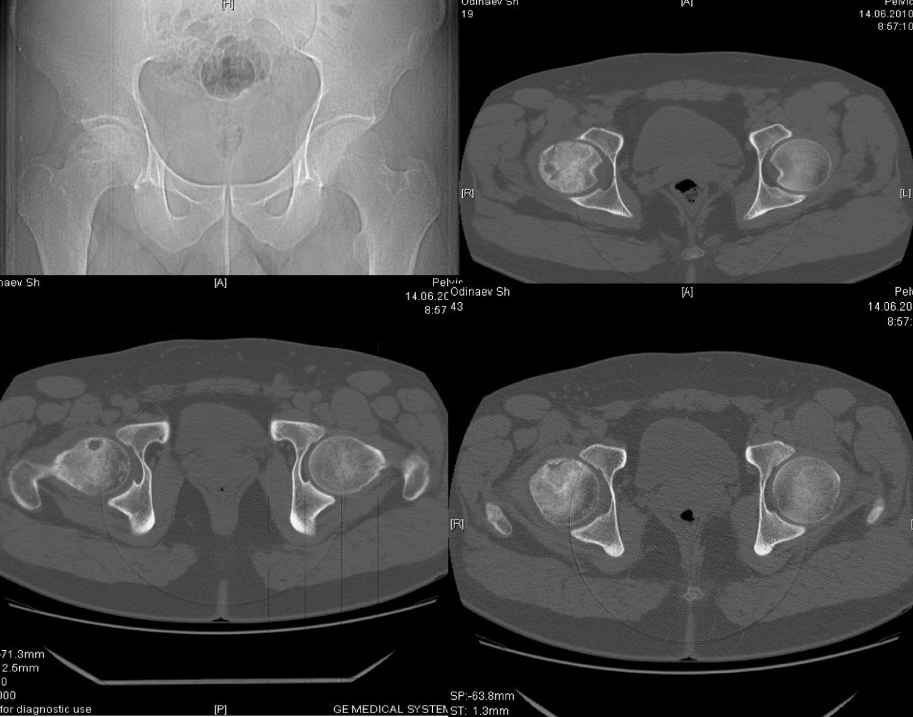

асептический некроз головки бедренной кости |

Обратился пациент,30 лет жалуется на боли в области правого т/бедренного сустава, хромоту.

При внутренней ротации болезнгенность.Болеет в течении 3 мес. Снимки во вложении. Больной получает курс консервативной терапии. Из хондропротекторов ДОНА порошок.

Хотелось бы услышать мнение уважаемого сообшесва по поводу консервативной терапии, может у кого из Вас имеется опыт по консервативной терапии с применением более эфективной медикаментозной терапии.

что касается эндопротезирования мы считаем, что в таком возрасте показания относительные.